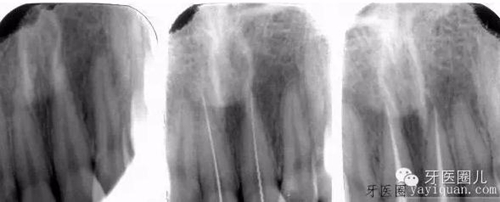

患者外傷11 21簡單冠折,選擇一次法完成冷牙膠充填3天后行樁修復(fù)。

一次法充填后最嚴(yán)重的疼痛發(fā)生在治療后24小時(shí)內(nèi),也有文獻(xiàn)說是6-8個(gè)小時(shí),隨后患者反應(yīng)會(huì)大大減輕,與多次法比較治療的并發(fā)癥和成功率沒有差別,這個(gè)病例次日電話回訪患者患者無不適。

個(gè)人介于器械和時(shí)間原因,一次法只做適應(yīng)癥范圍內(nèi)前牙,后牙基本都是2-3次完成治療。